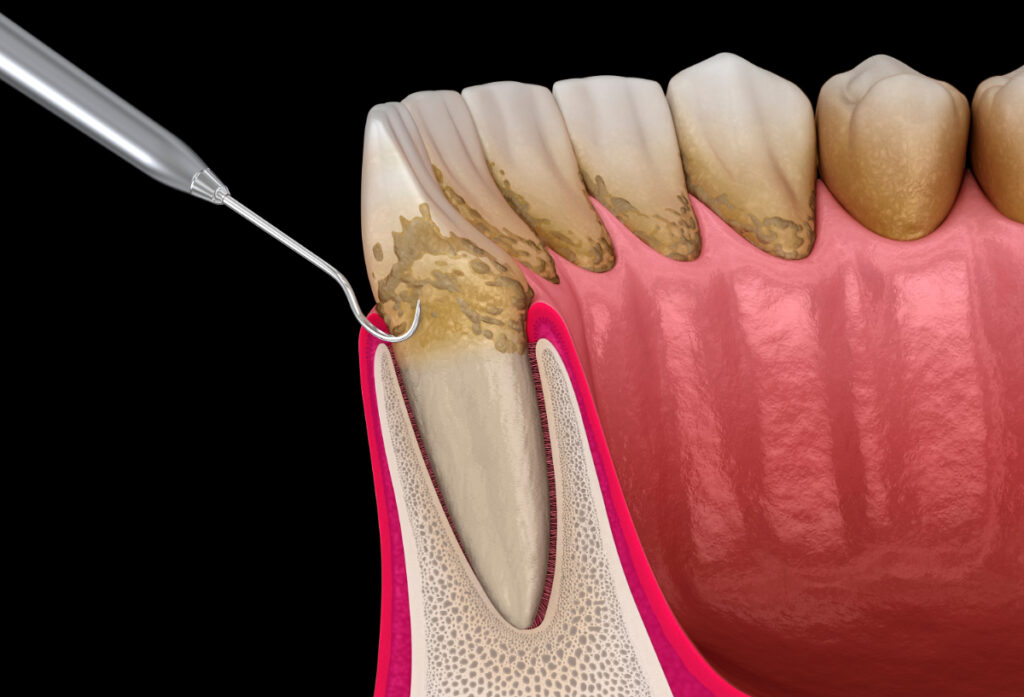

歯周病の様子

歯周病とは、歯を支えている歯槽骨や歯ぐきなどの歯周組織に炎症が生じる病気です。初期段階では歯肉炎と呼ばれ、歯ぐきに軽い炎症が起こります。やがて炎症が深部に進むと歯周炎へと進行して歯を支える骨が破壊されていき、最終的に歯を失うこともあります。

歯周病の主な原因

歯周病の主な原因は歯垢(プラーク)です。プラークとは細菌の塊のことで、歯と歯ぐきの境目に付着しやすく、これが時間とともに歯石へと変化します。プラークや歯石がたまると、細菌が出す毒素によって歯ぐきに炎症が広がり、歯周組織が破壊されていきます。

重度の歯周病の治療法

中等度までの歯周病であれば、歯石除去や日常的なケアの徹底などで改善が見込めますが、重度になるとそれだけでは追いつきません。歯周ポケットが6mm以上の状態では、歯の根の奥や歯ぐきの深部にまで汚れや細菌が入り込んでおり、通常のクリーニングでは取り切れないことが多いためです。

歯周外科治療

歯周ポケットが深い場合には、歯ぐきを切開して清掃を行う歯周外科治療が必要になります。歯周外科治療には、フラップ手術や歯周組織再生療法などがあります。以下でそれぞれを詳しく解説します。

フラップ手術

フラップ手術とは、歯ぐきを切開して歯の根元まで達している汚れや炎症組織を除去する治療法で、歯周ポケットの深さを浅くして再発を防ぐことが目的です。スケーリングやルートプレーニングでは取りきれなかった深い歯周ポケットに付着した歯石を、直接目で確認しながら徹底的に取り除きます。